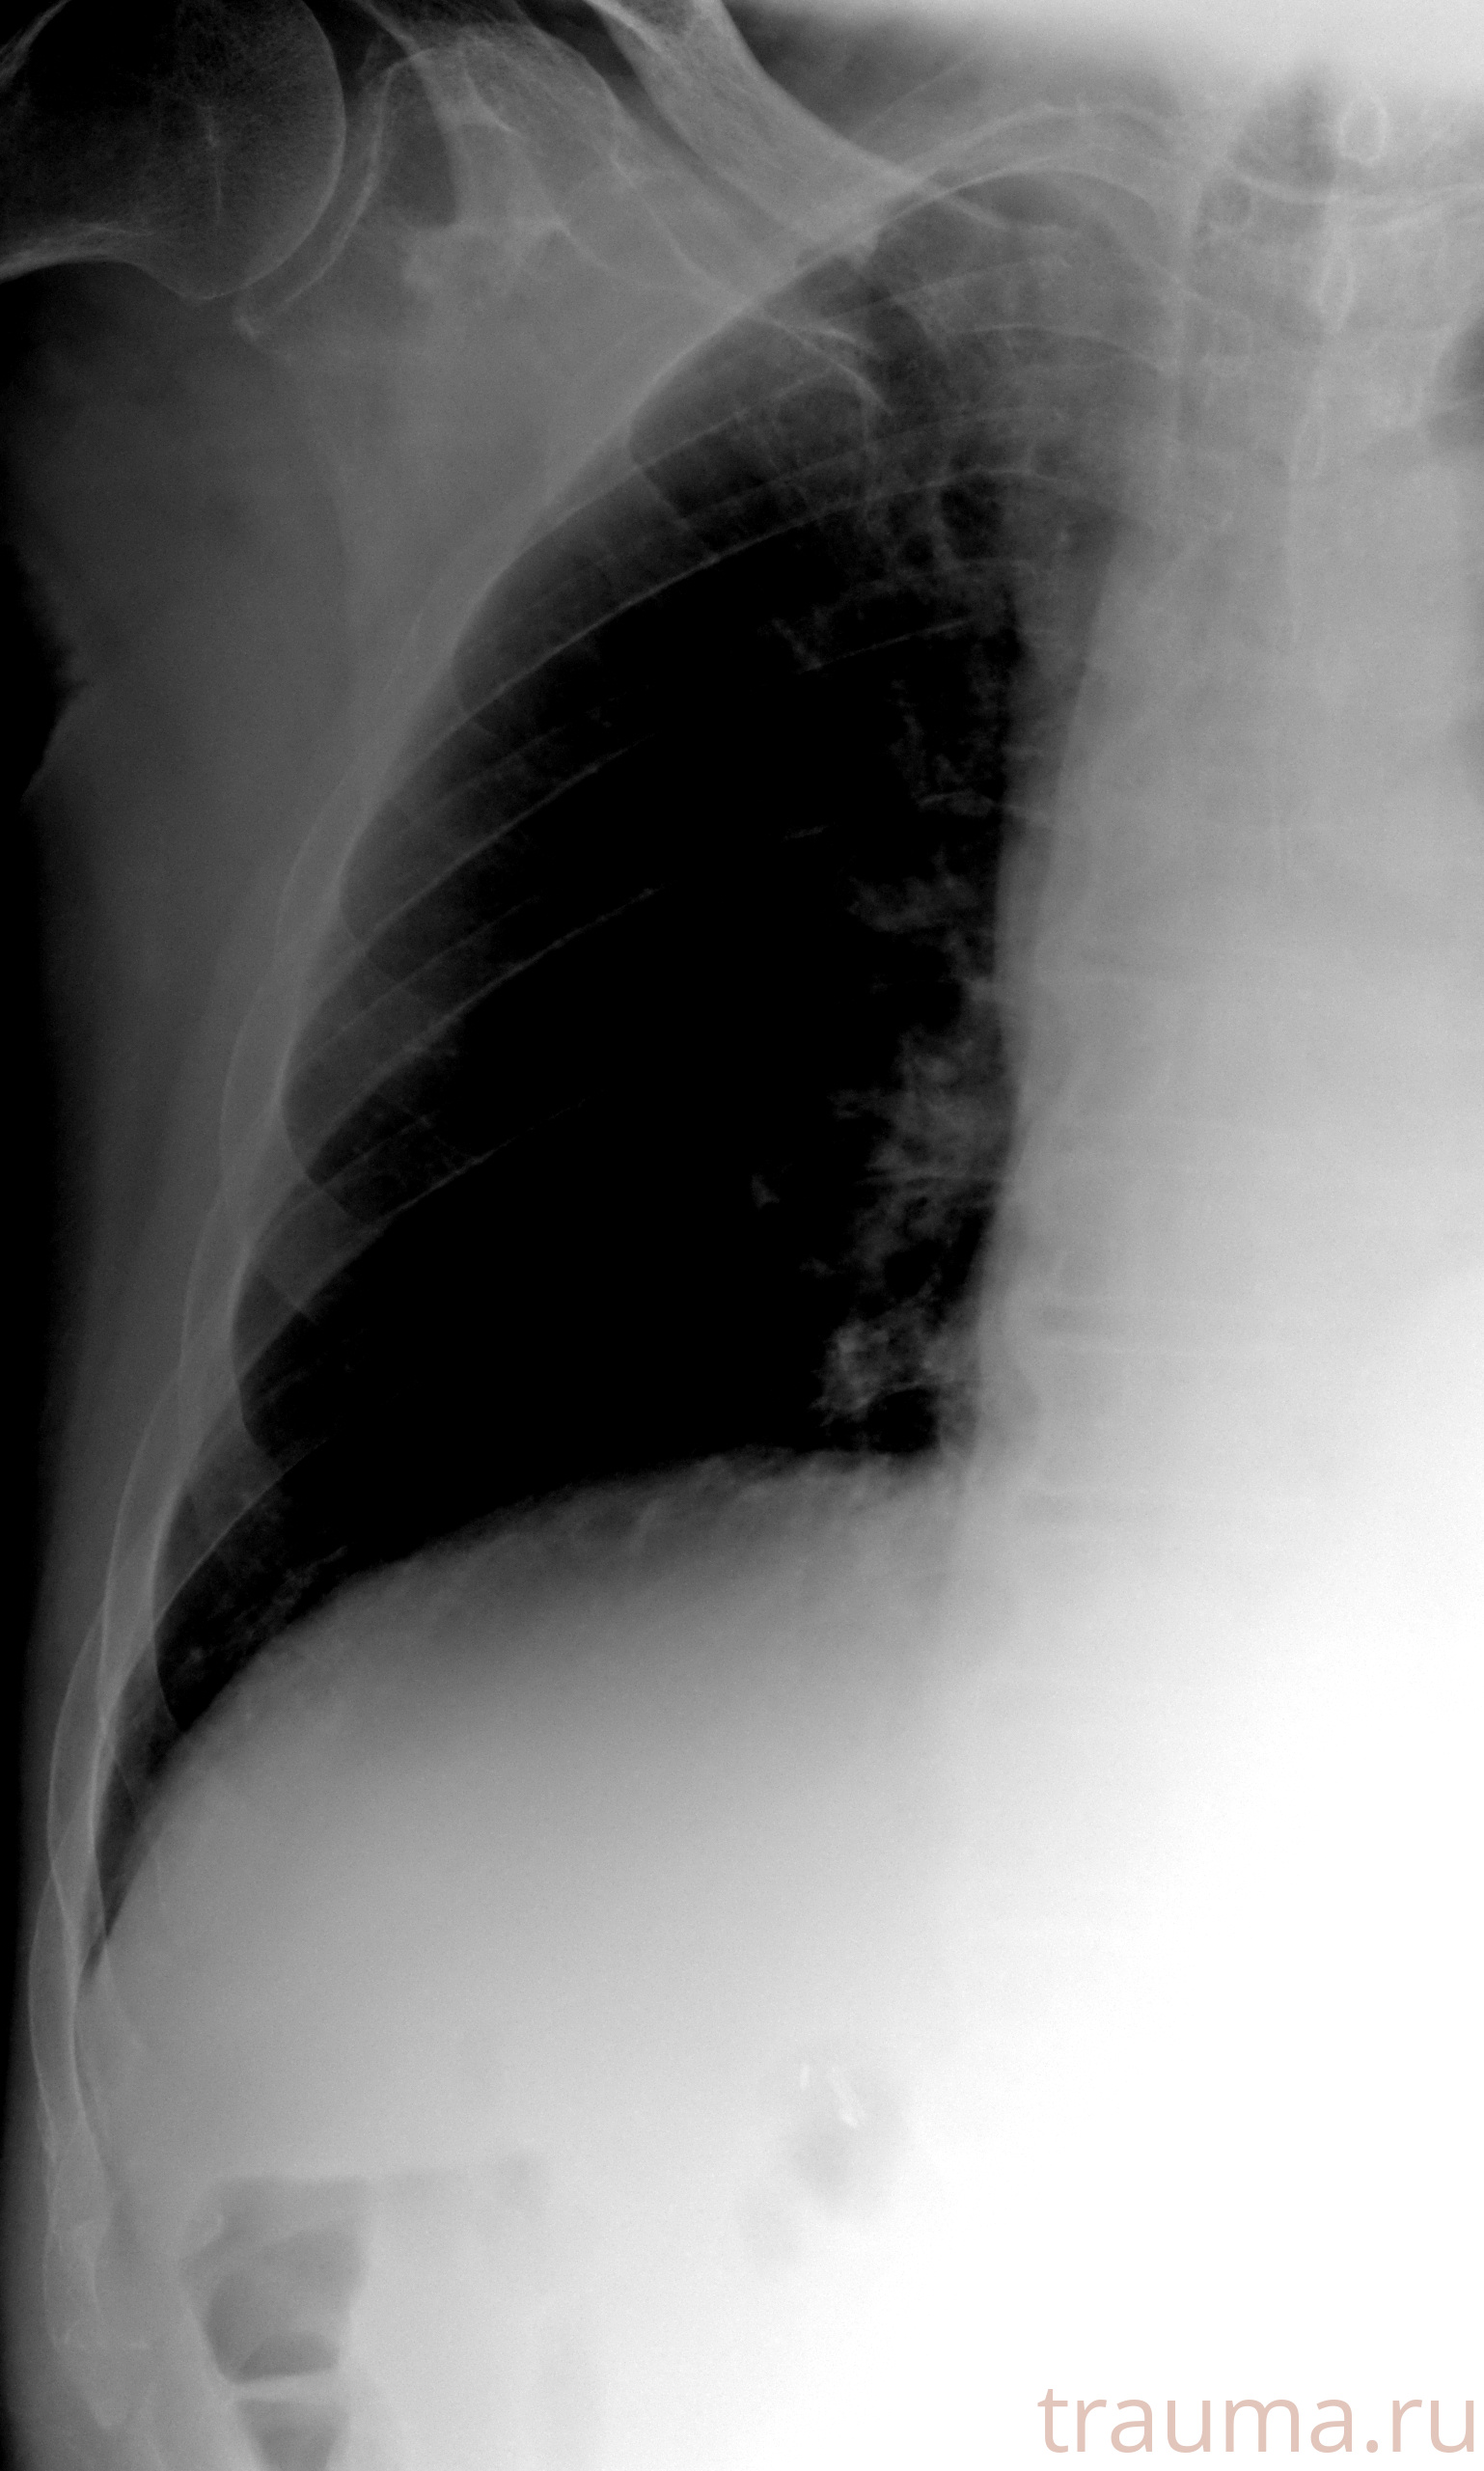

Рентген на дому: по вашему адресу приезжает врач-рентгенолог, травматолог-ортопед с мобильным рентгеновским аппаратом, проводит диагностику травмы или заболевания, делает необходимые рентгенограммы, дает рекомендации по дальнейшему лечению. Получить качественные снимки в домашних условиях возможно благодаря уникальной методике, разработанной МосРентген Центром для института  Склифосовского